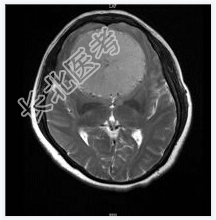

- [材料题] 患者女,55岁,视力下降数月。查体:视力下降,余神经体征阴性。

- 简答题1、诊断及依据是什么?

- 简答题2、鉴别诊断有什么?